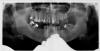

Саша-простокваша Опубликовано 2 февраля, 2011 Поделиться Опубликовано 2 февраля, 2011 (изменено) Добрый день.Прошу совета у специалистов.Была в двух клиниках. По жевательным зубам нижней челюсти в одной порекомендовали удалить все 4 ("все равно лежат") и поставить снизу по 3 импланта с каждой стороны. В другой сказали что удалить надо только разрушенный. Остальные можно подлечить/перелечить и поставить под коронки (коронки в этом случае, я так поняла будут под углом к корню), а в проем уже по 1-2 импланта. Я хочу узнать, какой вариант более "правильный"?Мне кажется, предпочтительнее оставить зубы, если у них корни нормальные. Но с другой стороны, нагрузка на эти корни при жевании будет нелинейная. Изменено 2 февраля, 2011 пользователем Саша-простокваша Ссылка на комментарий

Bier Опубликовано 2 февраля, 2011 Поделиться Опубликовано 2 февраля, 2011 на мой взгляд справа точно удалять, слева 50/50, я бы наверное советовал удалить. Для достижения оптимального результата с этим зубом надо потратить много сил, без гарантии, что все получится. Ссылка на комментарий